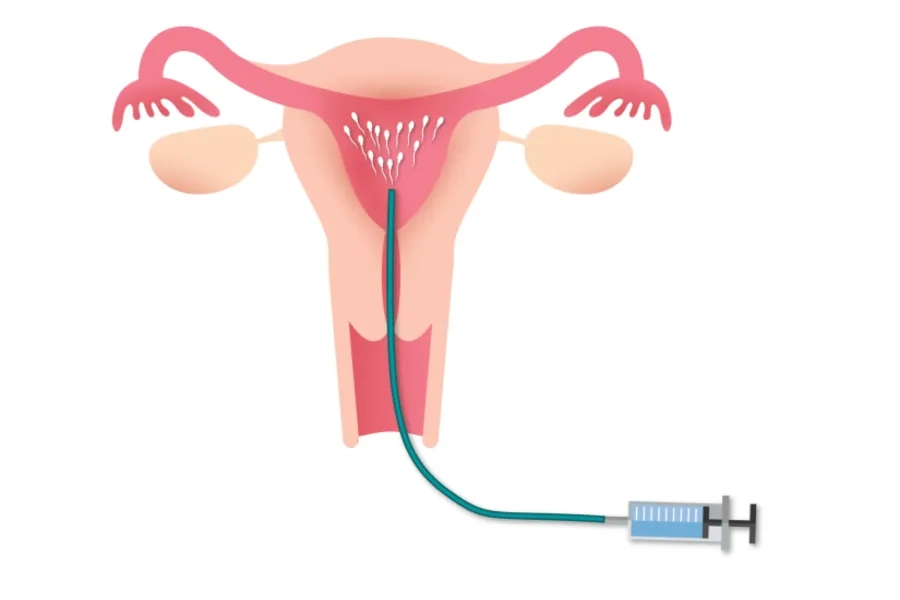

IUI (Intrauterine Insemination) - thụ tinh nhân tạo là kỹ thuật đưa trực tiếp tinh trùng đã được lọc rửa vào buồng tử cung của người phụ nữ. IUI giúp tinh trùng dễ dàng tiếp cận và thụ tinh với trứng, từ đó tăng cơ hội thụ thai. Phương pháp này thường áp dụng cho các cặp vợ chồng khó thụ thai do rối loạn phóng noãn, bất thường tinh trùng mức độ nhẹ hoặc vô sinh chưa rõ nguyên nhân.

IUI là phương pháp thụ tinh nhân tạo, bơm tinh trùng vào buồng tử cung

4. Bước 4: Thực hiện bơm tinh trùng

Bạn nên nằm ở tư thế giống khám phụ khoa. Tinh trùng đã lọc rửa được đưa vào tử cung bằng ống bơm chuyên dụng. Thủ thuật diễn ra nhanh chóng, chỉ mất khoảng 5 phút và hầu như không gây đau. Sau thủ thuật, bạn nên nghỉ ngơi khoảng 10-15 phút. Một số trường hợp có thể xuất hiện một lượng dịch âm đạo nhẹ do chất nhầy cổ tử cung hoặc dung dịch hỗ trợ bơm.

Kỹ thuật bơm tinh trùng vào buồng tử cung được thực hiện bởi đội ngũ bác sĩ chuyên khoa giàu kinh nghiệm